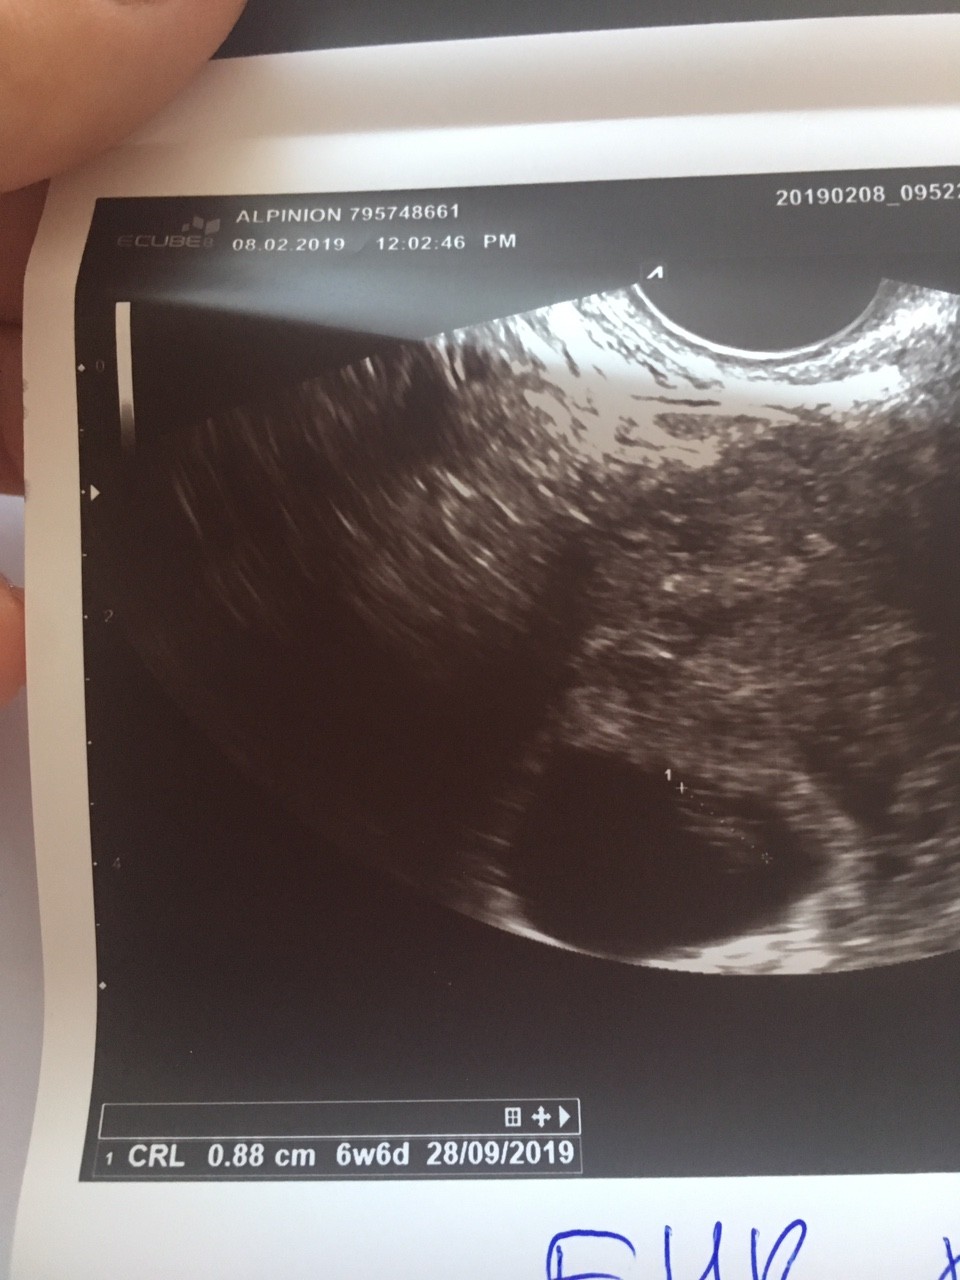

Dziękuję i gratuluję rownież dobrych wieści z podglądania Maluszków Zobacz załącznik 941062